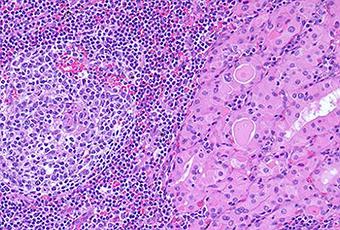

Mecanismo de la enfermedad y la histología

Tiroiditis de Hashimoto o la enfermedad de Hashimoto es un trastorno de la glándula tiroides común que puede ocurrir a cualquier edad, pero es más común en las mujeres de mediana edad. Es causada por una reacción autoinmune, una reacción del sistema inmune contra la glándula tiroides. Fisiológicamente, estos auto-anticuerpos están dirigidos contra la peroxidasa tiroidea y la tiroglobulina, que están provocando una destrucción gradual de los folículos en la glándula tiroides.

Esta enfermedad se caracteriza por:- Un intenso celular mononuclear que se infiltra en la glándula tiroides

- La presencia de autoanticuerpos

3. El examen histológicoEl examen histológico de la glándula se está haciendo mediante la eliminación de pequeñas cantidades de tejido tiroideo, ya sea con una biopsia con aguja o durante la cirugía. La muestra de tejido se envía entonces a los patólogos, que son capaces de ver la infiltración de linfocitos, usando microscopios.